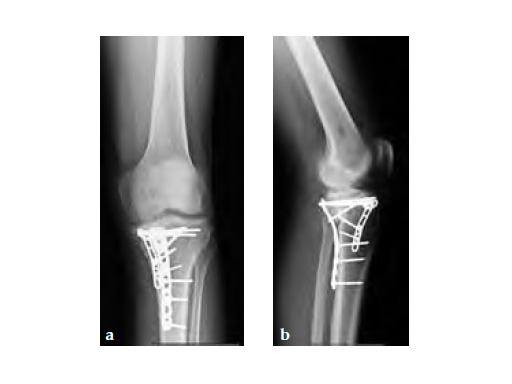

A 33-year-old male was involved in an altercation and suffered a gun shoot wound to his knee

Case provided by Brent Norris, Tulsa, USA.

Initially taken for incision and drainage and then ORIF . Patient placed in a floppy lateral position with the effected lower extremity externally rotated (opposite hip and shoulder bumped up about 3040) allowing exposure of the posterior medial knee. A posterior medial and an anteromedial incision were used to repair the fracture with a 67 cm skin bridge.

Postoperative healing was uneventful and the patient had no complications.